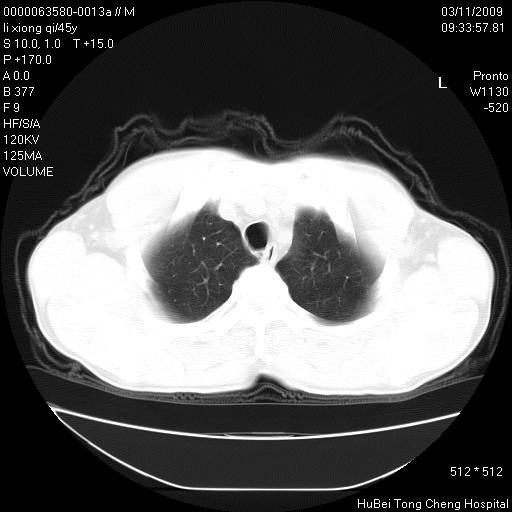

患者 男,45岁。胸痛,咳嗽伴痰中带血1月余。

临床诊断:肺结核?

胸部ct轴位平扫(层厚10mm,螺距1.5,重建间隔10mm),图像如下:

考虑肝癌肺转移